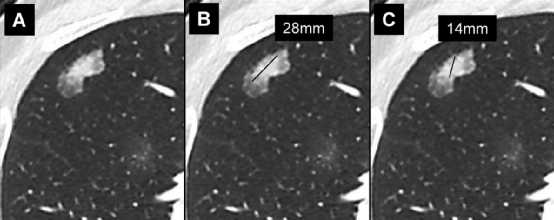

右肺上叶的实性结节 (箭头) 的时间顺序扫描。结节的平均直径为,A、8mm,B、9mm,C、11mm,D、13mm。当我们将最早的图像与最新的图像进行比较时,结节的生长最为明显。手术证实为腺癌。